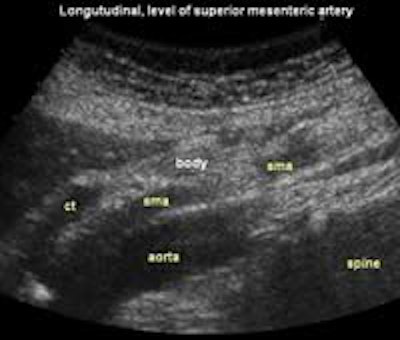

Longitudinal planes from right to left:

![]() Image22 |